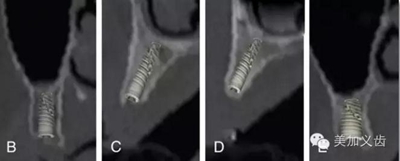

值得注意的是:使用根尖片來進行術(shù)后隨訪,這是種植術(shù)后很重要的一件事情,而且需要定期來做,然后將拍攝出來的根尖片進行對比,才能看到是否有骨吸收。但如果你每次拍攝的角度都不一樣,結(jié)果會讓你嚇一跳,怎么某段時間內(nèi)骨吸收這么多?!怎么某段時間骨頭又長上來了?!太令人費解了!

3.jpg

其實是你拍攝的角度不一樣,所得到的結(jié)果也不一樣,因此,采用平行透照技術(shù)就十分關(guān)鍵,否則你的術(shù)后回訪是沒有意義的。平行透照技術(shù)很簡單,通過X線片定位器就可以做到,讓你的X線接收器和管球平行,這樣每次拍攝的角度都是一樣的了。